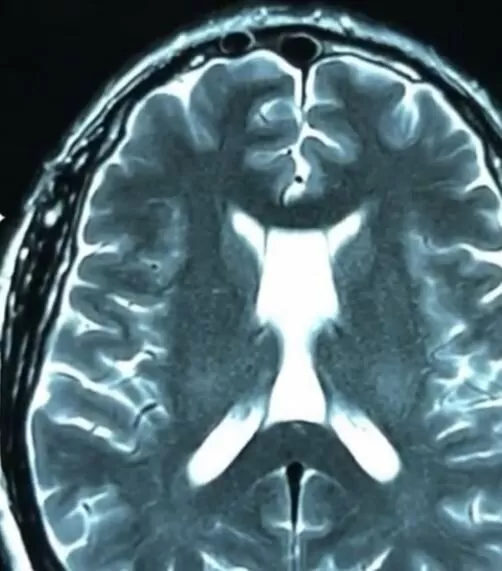

Arachnoid cysts of the transparent membrane of the brain – this is a pathological benign volume formation which

represents splitting of the transparent membrane with compression of both lateral ventricles of the brain.

MRI is a verification method for diagnosing arachnoid cysts of the transparent membrane of the brain

and/or CT scan of the brain.